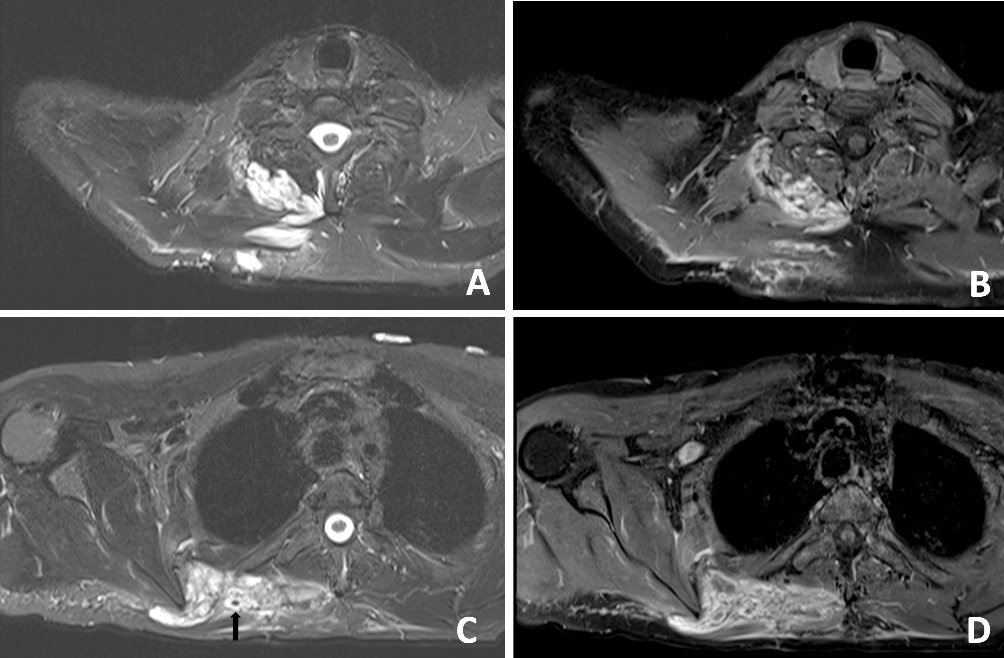

The patient remained febrile until day four post washout. Histopathology was inconclusive and a further sample was recommended if clinical uncertainty remained. An MRI performed one week following the initial presentation demonstrated a trans-spatial low-flow VM within the anterior and medial compartments of the thigh. On post-contrast T2 images, there were two thick-walled peripherally-enhancing fluid collections that were interpreted as infected collections (pyomyositis).

A subsequent washout was performed on day three; intraoperative findings were similar to the first operation. The patient’s fever subsequently settled. An MRI was performed on day 11 to evaluate for possible VM or sarcoma. An MRI revealed a ‘trans-spatial right paraspinal mass involving the trapezius and rhomboid muscles with internal phleboliths, no fluid levels or flow voids, in keeping with a slow flow vascular malformation’ (Figure 4).

In retrospect, the presence of intramuscular phleboliths on CT in the cases presented above was the best clue to the diagnosis of an infected VM. Phleboliths occur in approximately 30 per cent of VMs.15 Intramuscular phleboliths have a limited imaging differential diagnosis and are generally taken to be pathognomic of VM.16 Radiologist and clinician awareness of this rare presentation of VMs is important; if intramuscular phleboliths are identified, the diagnosis of VM should be raised and the use of MRI may further assist in the diagnosis. If clinical doubt remains in an acutely unwell patient, prompt surgery to exclude necrotising soft tissue infection is prudent.